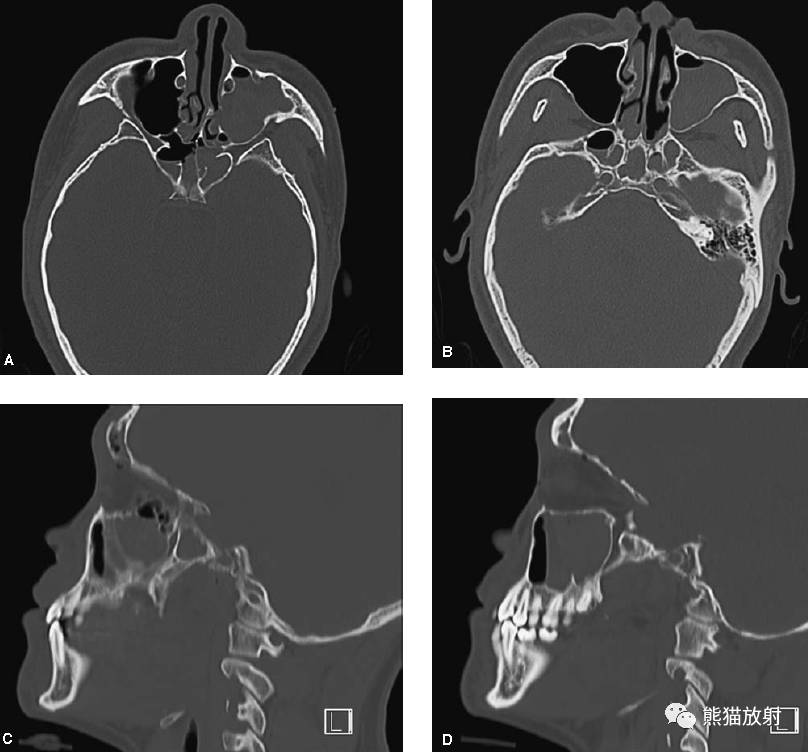

【急诊】颧骨骨折,上颌骨骨折ct表现_医学界-助力医生临床决策和职业

颧骨骨折

颧弓骨折一例

夜班不求人——颅骨骨折(下)_颧骨